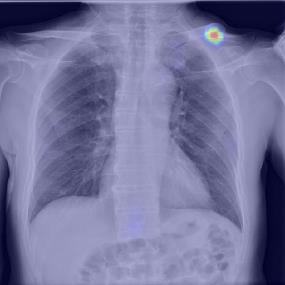

Chest X-ray (CXR) is the most typical diagnostic X-ray examination for screening various thoracic diseases. Automatically localizing lesions from CXR is promising for alleviating radiologists' reading burden. However, CXR datasets are often with massive image-level annotations and scarce lesion-level annotations, and more often, without annotations. Thus far, unifying different supervision granularities to develop thoracic disease detection algorithms has not been comprehensively addressed. In this paper, we present OXnet, the first deep omni-supervised thoracic disease detection network to our best knowledge that uses as much available supervision as possible for CXR diagnosis. We first introduce supervised learning via a one-stage detection model. Then, we inject a global classification head to the detection model and propose dual attention alignment to guide the global gradient to the local detection branch, which enables learning lesion detection from image-level annotations. We also impose intra-class compactness and inter-class separability with global prototype alignment to further enhance the global information learning. Moreover, we leverage a soft focal loss to distill the soft pseudo-labels of unlabeled data generated by a teacher model. Extensive experiments on a large-scale chest X-ray dataset show the proposed OXnet outperforms competitive methods with significant margins. Further, we investigate omni-supervision under various annotation granularities and corroborate OXnet is a promising choice to mitigate the plight of annotation shortage for medical image diagnosis.